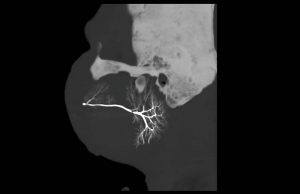

3. Sialography – This is a specialized imaging technique proposed only for assessing the morphology and functionality of the parotid and submandibular glands. The principal indication for sialography is chronic inflammatory conditions especially where there is obstruction as in Sjogren's syndrome. The technique involves infusion of the gland ductal system with an iodinated contrast agent, and then imaging the gland with projection imaging, fluoroscopy, or cone beam computed tomography (CBCT).